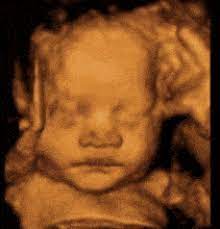

5d Hd Live Ultrasound 4d Ultrasound 3d Ultrasound Sonogram In Phoenix

5d Hd Live Ultrasound 4d Ultrasound 3d Ultrasound Sonogram In Phoenix from www.4dsono.com